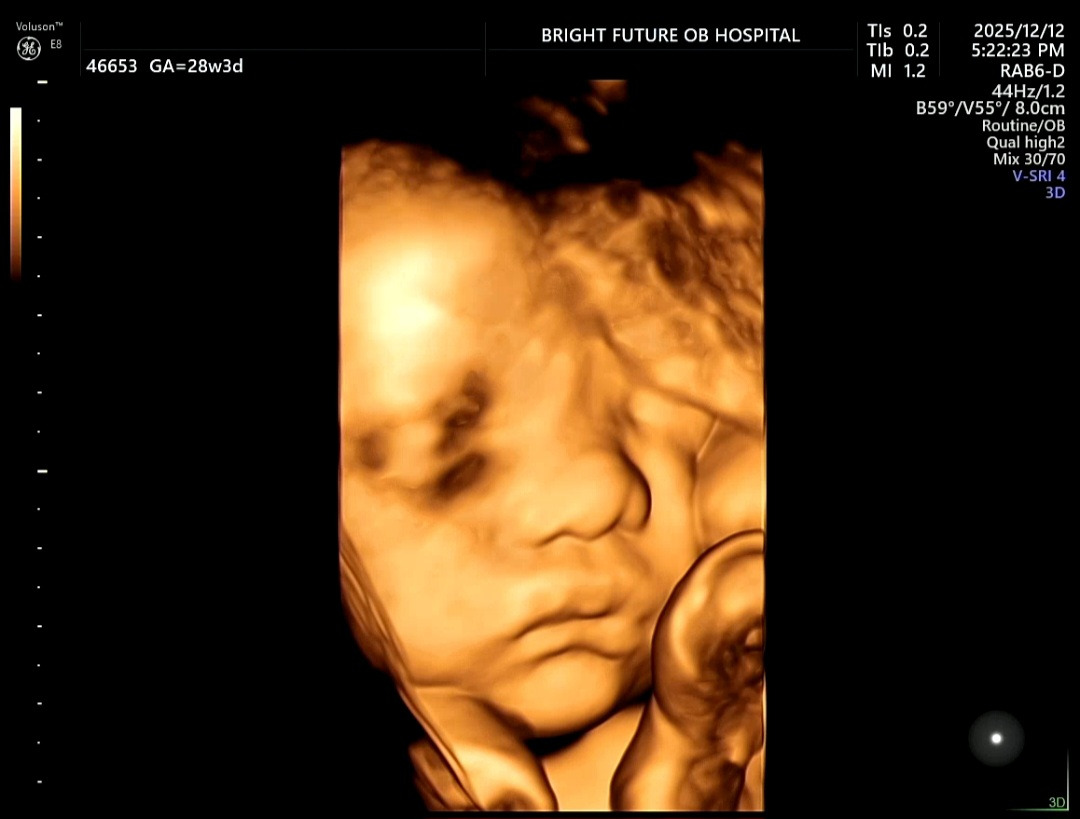

보통 28~30주 사이는

- 얼굴에 지방이 붙기 시작하고

- 볼살, 입술, 코 윤곽이 살아나서

입체초음파로 가장 ‘아기다운 얼굴’을 보기 좋은 시기라고 한다.

그런데 이번 28주 입체초음파는 완전히 달랐다.

“아, 이래서 다들 이 시기에 입체초음파를 보나 보다” 싶을 정도로

아가아가한 얼굴이 딱 나타났다.

초음파 화면 속에서

‘내 배 속에 정말 사람이 자라고 있구나’

라는 생각이 들면서 말할 수 없는 감정이 느껴졌다.

임신이라는 게 참 경이롭고 신비한 경험이라는 걸 다시 느낀다.